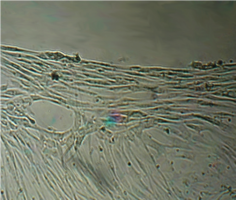

7 серия экспериментов. Образец исследуемого материала (фрагмент стержня из титана - диск диаметром 3 мм, толщиной 2 мм и массой 65 мг) помещали на равномерный монослой фибробластов плотностью 332 клетки/ммІ.

При световой микроскопии все поверхности диска выглядели гладкими и блестящими.

Через сутки обращало на себя внимание нарастание плотности монослоя в непосредственной близости от образца.

Более того, в ходе эксперимента фибробласты прилипали к ребру образца и поднимались по нему вверх, образуя по всему периметру диска утолщение в виде валика (рис 36).

Сцепление клеток с металлом было столь прочным, что уже на 3 сутки опыта образец оставался неподвижным на дне культуральной чашки при любом изменении ее положения (вплоть до того, что чашку можно было перевернуть вверх дном и держать так неограниченное время – рис. 37).

На всей остальной поверхности дна опытной чашки  монослой был целостным и равномерным, фибробласты сохраняли обычную структуру, форму и размеры.

Вид монослоя и структура клеток не отличались от обычных в течение всех четырех суток наблюдения.

Количество поврежденных клеток было в пределах 2-5%.

Плотность монослоя и время удвоения культуры в контроле и опыте отличались незначительно (табл. 15).

В 7-8 сериях экспериментов образцами исследуемого материала послужили фрагменты титанового стержня - диски диаметром 3 мм, толщиной 2 мм.

Уже через сутки обращало на себя внимание нарастание плотности монослоя в непосредственной близости от образца.

Более того, в ходе эксперимента фибробласты прилипали к ребру образца и поднимались по нему вверх, образуя по всему периметру диска утолщение в виде валика.

Сцепление клеток с металлом было столь прочным, что уже на 3 сутки опыта образец оставался неподвижным на дне культуральной чашки при любом изменении.

Плотность монослоя и время удвоения культуры в контроле и опыте отличались незначительно.